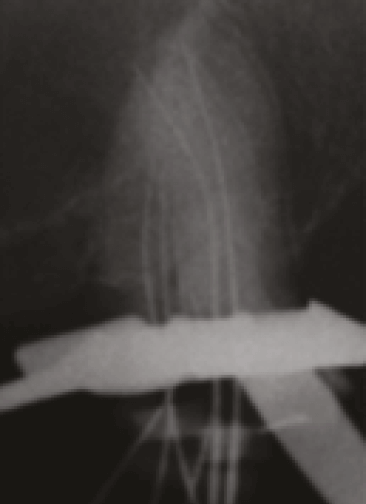

En la siguiente consulta se realizó preparación química del SCR con hipoclorito de Sodio al 5.25%, solución fisiológica y EDTA al 17%. Se secó el SCR con conos de papel estériles. Obturación con gutapercha y cemento sellador AH Plus (Dentsply Maillefer, Ballaigues, Suiza) con técnica de compactación vertical de onda continua (System B Cordless, Sybron Endo, Orange, California), (Figura 4), restauración con resina fluida de color morada (perma flow purple, Ultradent, Utah, USA) e ionómero de vidrio, a la espera de recostrucción definitiva. Se realiza reevaluación a 18 meses posterior a la culminación del tratamiento de conductos, se presenta asintomático y se realizó reconstrucción definitiva con perno de fibra de vidrio intrarradicular en conducto P y prótesis provisional, Figura 5.

Figura 5. Rx final orto (a), distorradial (b) y rx de reevaluación a 18 meses de control (c).

En el presente caso la utilización de microscopio óptico operatorio junto con la toma de radiografías, durante el desarrollo de la terapia endodóntica, ayudaron a entender la compleja variación anatómica del SCR, confirmando la presencia de 6 conductos radiculares (4 conductos en la raíz MV, 1 en la raíz DV y 1 en la raíz P). Figura 6.

Figura 6. a) Imagen clínica a 5X magnificación de obturación del SCR. b) Rx de obturación definitiva y representación esquemática de configuración de conductos en raíz MV (color rojo).